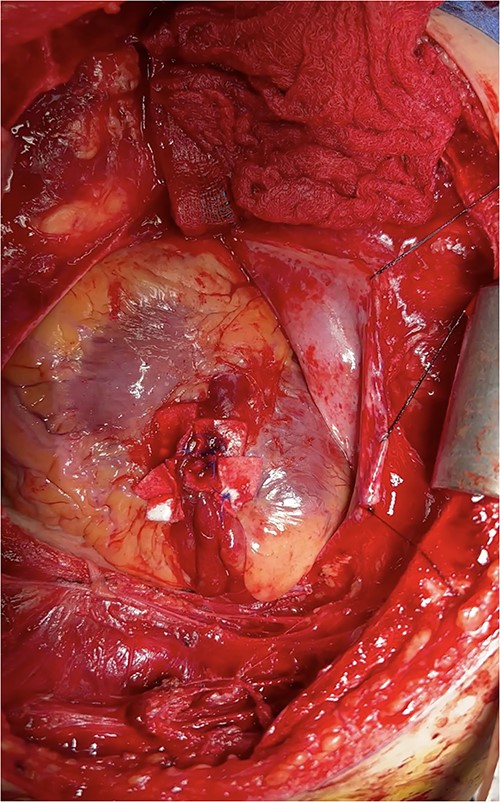

At this time, the trauma surgeons decided to take the patient emergently to the operating room. We performed a median sternotomy and discovered a 4-cm laceration of the pericardium (see Fig. 4) and left mediastinal pleura, moderate hemopericardium with thrombus, and 3-cm rupture of the right ventricle adjacent to the left anterior descending artery, consistent with the CT scan. Approximately, 2 cm of this injury was full-thickness and the remaining 1 cm was partial thickness involving most, but not the entirety, of the ventricular wall (see Supplementary Intra-Operative Video). The right ventricular injury was repaired primarily using pledgeted 3-0 prolene horizontal mattress sutures (see Fig. 5). The ventricle was hemostatic and noted to have good contractility. At this time, we performed a diagnostic laparoscopy to rule out a possible left diaphragmatic injury noted on CT. A grade I segment VII hepatic laceration was identified that was managed laparoscopically with hepatorrhaphy using electrocautery.

Intraoperative photo demonstrating extravasation from ventricular rupture.